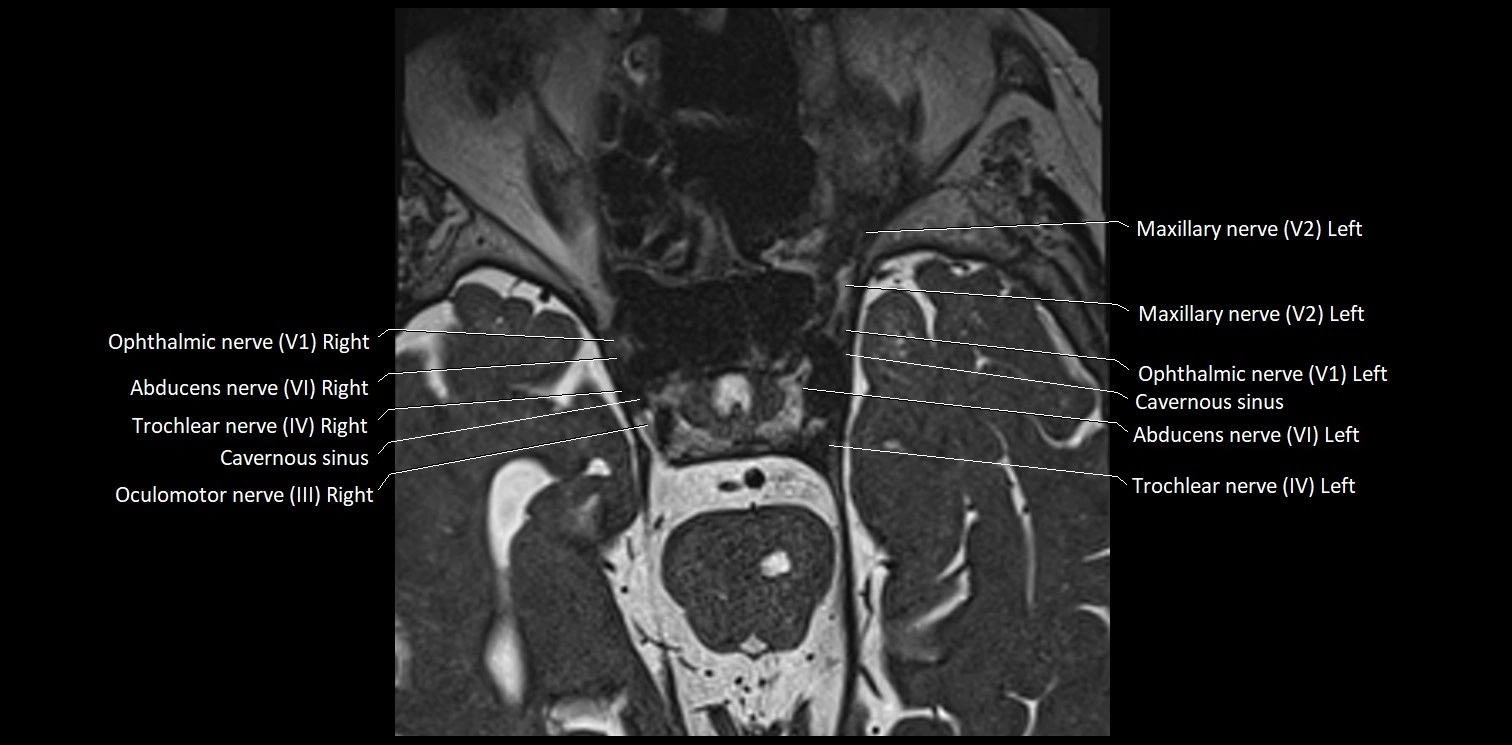

MRI Appearance

• The abducens nerve is a small, thin, linear structure

• Best visualized on high-resolution T2-weighted 3D MRI sequences (e.g., FIESTA or CISS)

• Seen as a hypointense (dark) line running from the brainstem at the pontomedullary junction, traversing the prepontine cistern, and entering Dorello’s canal under the petrosphenoidal ligament, then into the cavernous sinus, and finally the orbit

• May be challenging to visualize in standard MRI due to its small size

• Pathology may be inferred by absence, displacement, or enhancement of the nerve

MRI images

image